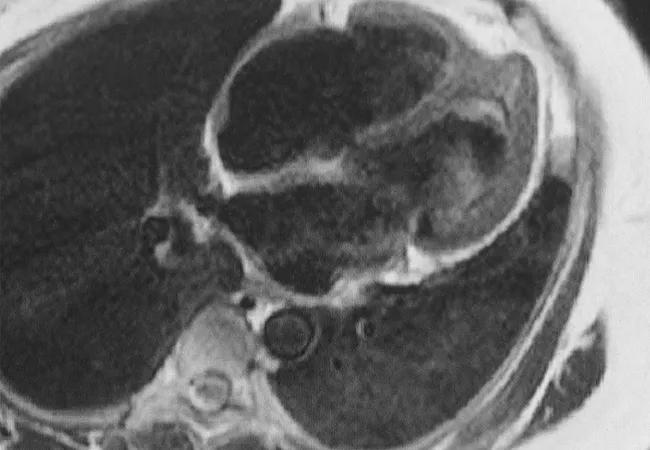

Feature image: Cardiac MRI demonstrating complications from heart involvement in EGPA (Churg-Strauss). This patient has endomyocardial fibrosis at the left ventricular apex with a large apical thrombus. Image and caption reprinted with permission from Elsevier.